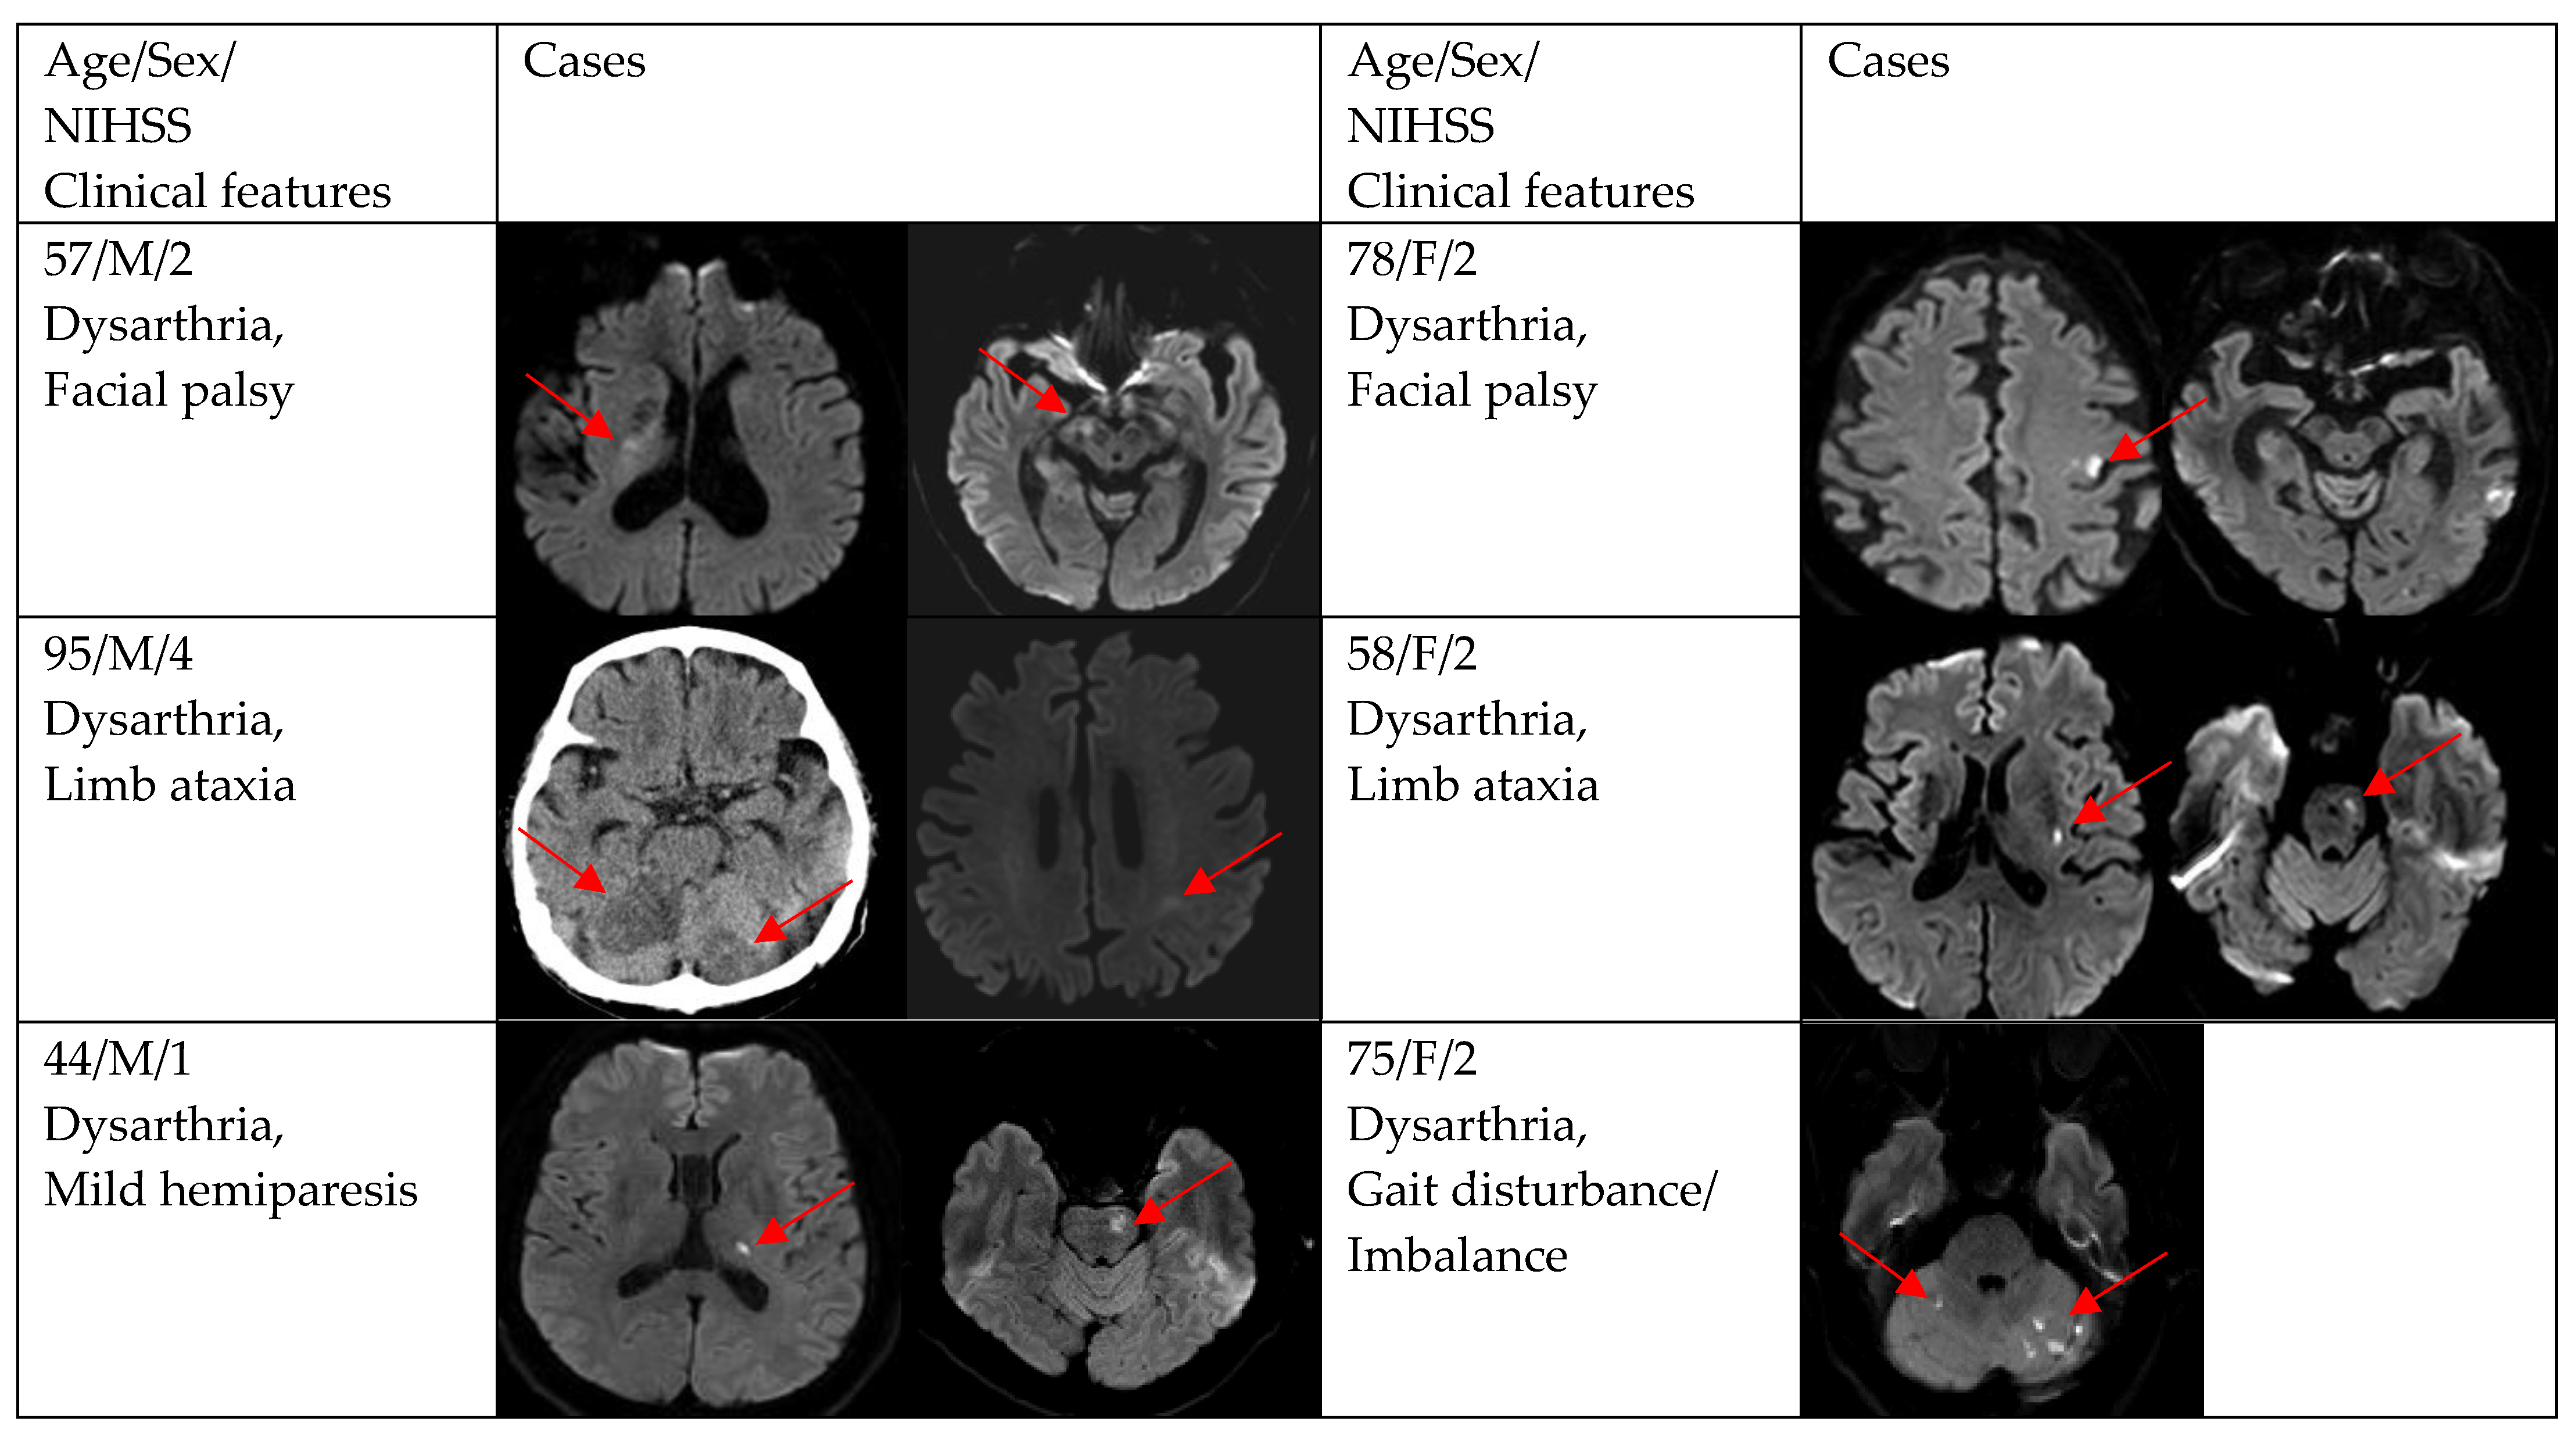

| Gait disturbance/imbalance | 9 (19.2) | 1 (7.7) | 8 (23.5) |

| Facial palsy | 8 (17.0) | 1 (7.7) | 7 (20.6) |

| Mild hemiparesis | 5 (10.6) | 2 (15.4) | 3 (8.8) |

| Dizziness | 4 (8.5) | 3 (23.1) | 1 (2.9) |

| Limb ataxia | 3 (6.4) | 0 (0.0) | 3 (8.8) |

| Transient motor weakness | 3 (6.4) | 0 (0.0) | 3 (8.8) |

| Headache | 1 (2.1) | 0 (0.0) | 1 (2.9) |

| Blurred vision | 1 (2.1) | 0 (0.0) | 1 (2.9) |

| DWI positivity | 12 (66.7) | 29 (87.9) | 0.154 |

| Single and small lesion | 10 (83.3) | 16 (55.2) | |

| Multiple or territorial lesions | 2 (16.7) | 13 (44.8) | |

| NIHSS at admission to ED in DWI positivity | <0.001 | ||

| 2 | 0 (0.0) | 14 (48.3) | |

| 3 | 0 (0.0) | 5 (17.2) | |

| 4 | 0 (0.0) | 3 (10.3) | |